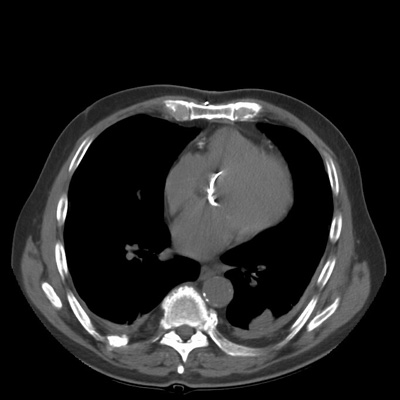

Rounded atelectasis in a patient with prior granulomatous infection

Asbestos related pleural disease is not the only cause of rounded atelectasis. The patient shown in the images below had a prior granulomatous infection with densely calcified left hilar adenopathy. There is extensive plerual thickening seen along the left anterior pleural surface. Rounded consolidated lung can be seen to abut this area of pleural thickening. Lung markings "swirl" into the area of abnormality. There is shift of the mediastinal structures to the left consistent with volume loss.